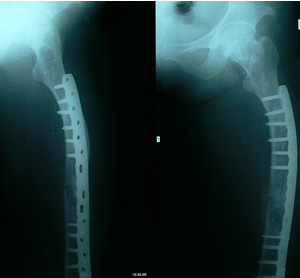

普通治療多採取病段切除後行帶血管的骨瓣移植、搔刮後植骨等治療。但是植骨後由於各種因素影響植骨存活,新植骨與囊壁的融合連線困難,難以修復。多骨型伴病理性骨折治療就更為困難。中藥治療骨纖維異常增殖症主要是調理內分泌,改善重建微循環,激活成細胞生長。它能使囊腔和瀰漫的骨溶解區逐漸修復,骨小梁由稀疏變為緻密,骨皮質逐漸增厚。最新套用Ilizarov技術,病灶段切除,自正常骨組織處延長再生能較快的徹底治療骨纖維異常增殖症。